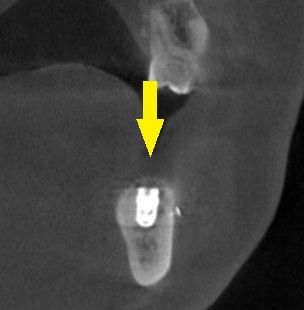

下の写真3段目が手術後のCTです。

インプラントと神経までの距離は確保され、インプラント上方は人工骨で覆われています。